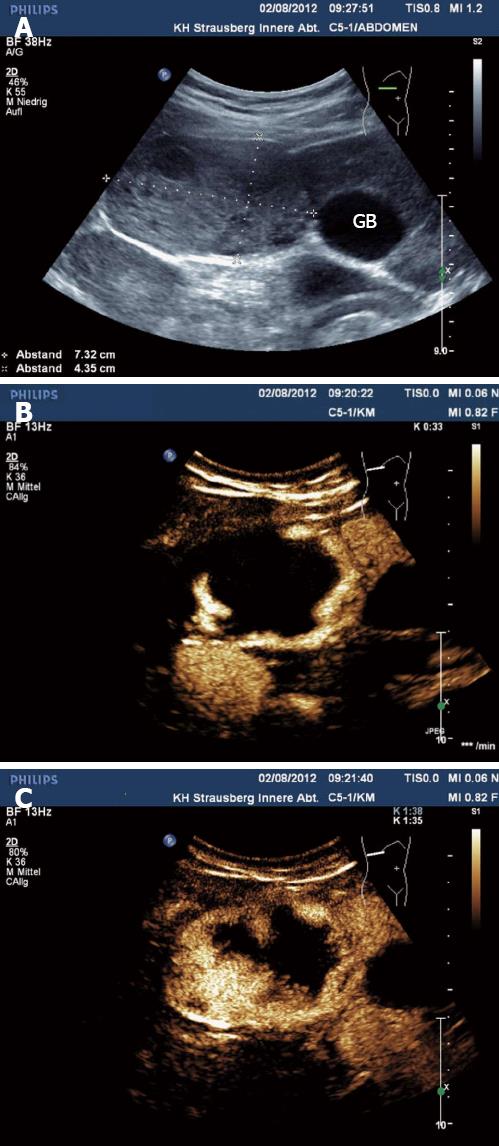

Hình 2

Hình 3

Đầu tiên, bệnh nhân được đưa vào một bệnh viện, sau đó siêu âm bụng và chụp cắt lớp vi tính ổ bụng (CT-scanner) được thực hiện. Siêu âm cho thấy một khối thương tổn [38 × 29 mm]. Các hình ảnh CT-scanner xác nhận phát sự hiện diện của khối này bằng cách tìm ra được một khối [3 × 4 cm] giảm dần đậm độ về trung tâm, tổn thương ở thùy trái của gan. Ngoài ra, ở vùng rốn gan, có hạch bạch huyết 31 mm đã được xác định.

Bệnh nhân sau đó được ra viện và yêu cầu tái khám 3 tháng sau để theo dõi diễn tiến. Kết quả của một CT-scanner khác sau đó cho thấy sự phục hồi cả khối u và các hạch lympho rõ ràng trên hình A và B.

Hình (A): Chụp CT-scanner ổ bụng kiểm tra cho thấy một khối thương tổn giảm âm, giảm dần độ đậm về trung tâm 7 × 5,5 cm trong nhu mô gan.

Hình (B): Một hình ảnh CT scanner khác cho thấy sự phục hội và xóa mờ các “khối u” ở trong nhu mô gan.